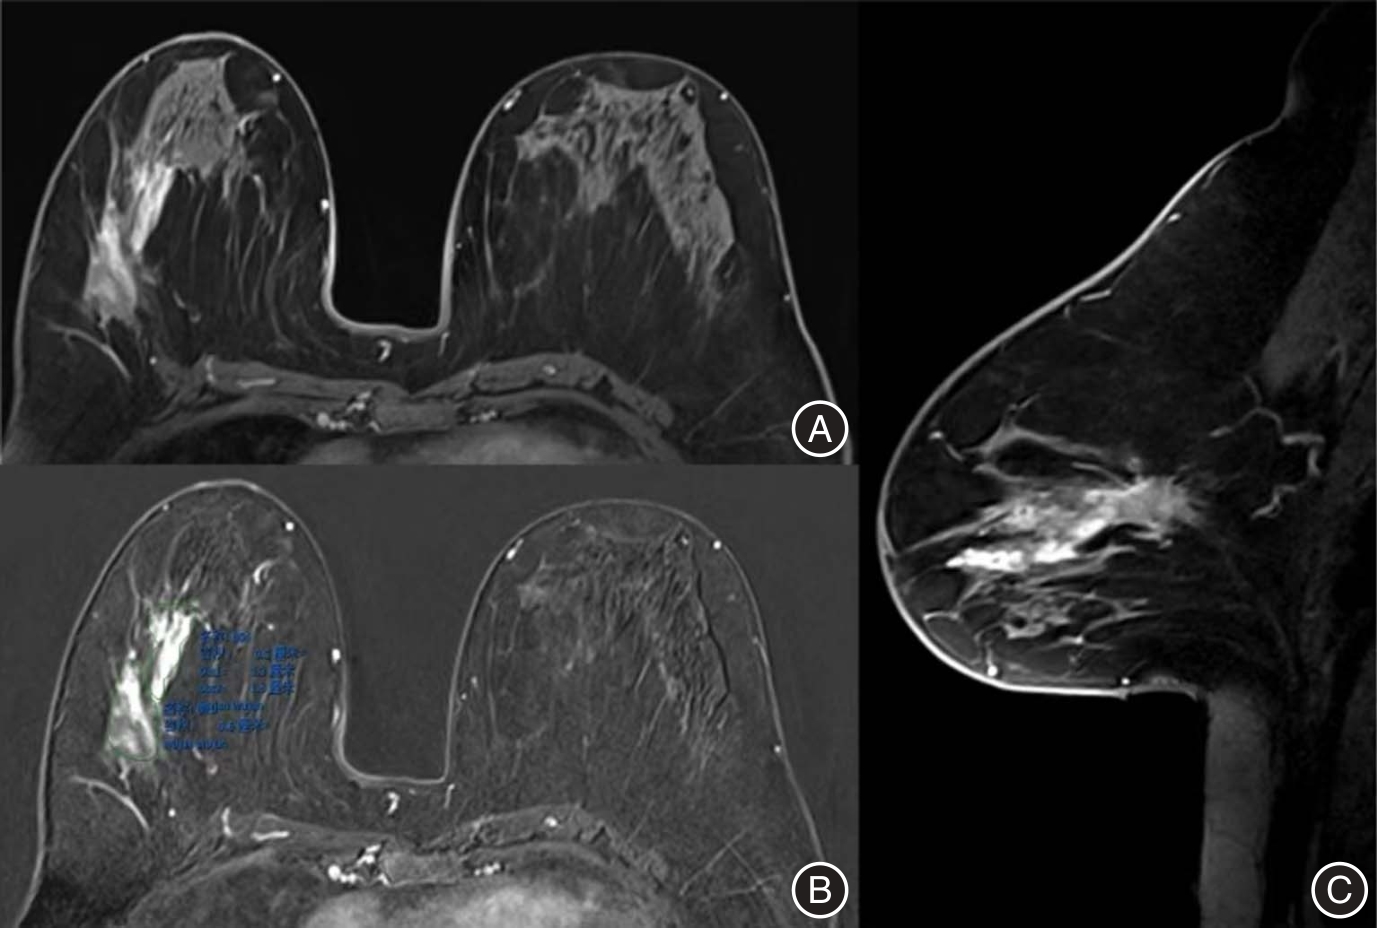

目的 比较乳腺磁共振(MRI)三种测量方法——RECIST 1.1标准、最优法和三维(3D)体积测量法在乳腺癌新辅助化疗(NAC)疗效评估中的诊断性能差异,筛选更具临床实用性的影像学评估方式。 方法 纳入2019—2023年间接受NAC及手术治疗的乳腺癌患者110例。化疗前后分别于1周内完成乳腺MRI,采用RECIST 1.1、最优法和3D体积测量法进行疗效评估,以MP病理分级为金标准。比较3种方法的敏感度、特异度、准确性及受试者工作特征曲线(ROC)下面积(AUC),并通过Delong检验进行统计比较。 结果 RECIST 1.1、最优法和3D测量法的AUC分别为0.768、0.795和0.883,3D体积测量法显著优于其他两种方法(P < 0.05)。3D法在敏感度(98.9%)、特异度(77.8%)和准确性(95.5%)方面均表现最优。最优法在部分指标上亦优于RECIST 1.1。 结论 3D体积测量法在乳腺癌NAC疗效评估中显示出最佳的诊断性能,具有更高的临床应用价值。最优法相较于传统RECIST 1.1方法也表现出更优的判别能力,是资源受限情况下的可行替代方案。

Objective To compare the diagnostic performance of three breast MRI measurement methods—RECIST 1.1, the optimal method, and three-dimensional (3D) volumetric assessment—in assessing the efficacy of neoadjuvant chemotherapy (NAC) in breast cancer patients, with the objective of identifying the most clinically practical approach. Methods A total of 110 breast cancer patients who underwent NAC followed by surgical treatment between 2019 and 2023 were included in the study. Breast magnetic resonance imaging (MRI) was conducted within one week before and after the completion of NAC. Tumor response was evaluated using RECIST 1.1 criteria, widely recognized as the optimal method, as well as 3D volume measurement. Pathological response was determined according to the Miller-Payne grading system. Sensitivity, specificity, accuracy, and the area under the receiver operating characteristic curve (AUC) were computed and compared using the DeLong test. Results The AUC values for RECIST 1.1, the optimal method, and 3D volumetric assessment were 0.768, 0.795, and 0.883, respectively. The 3D volumetric assessment exhibited significantly better discriminative performance (P < 0.05), with the highest sensitivity (98.9%), specificity (77.8%), and accuracy (95.5%). Additionally, the optimal method demonstrated superior performance over RECIST 1.1 across multiple parameters. Conclusions 3D volumetric measurement demonstrates superior performance compared to RECIST 1.1 and the optimal method in evaluating the response to NAC, offering a more accurate and comprehensive assessment tool. Additionally, the optimal method shows advantages over RECIST 1.1 and may serve as a practical alternative in settings where 3D software is not available.